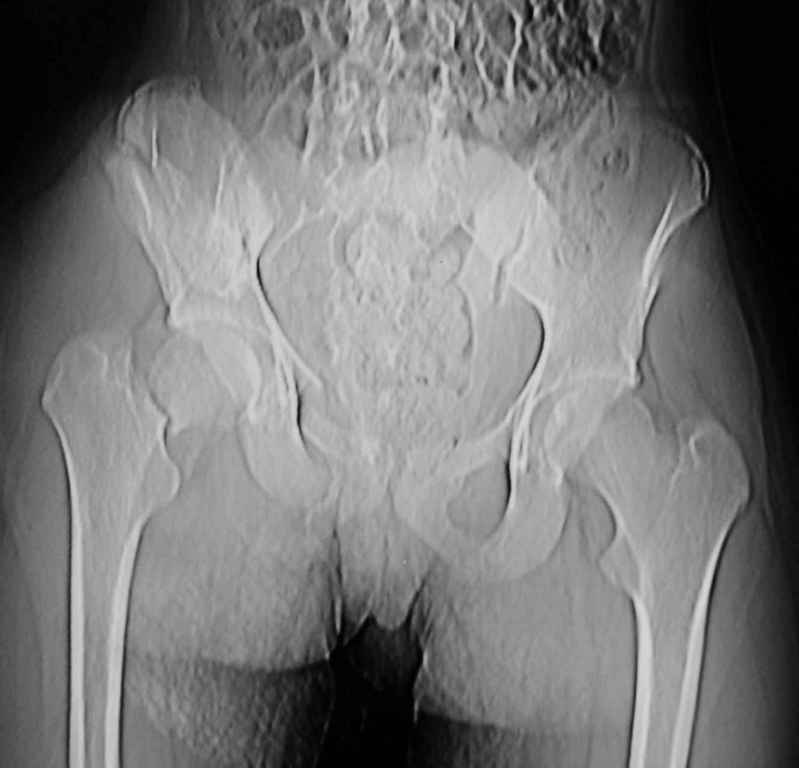

Уважаемый Алексей, на представленных Вами снимках имеется вертикально-нестабильное повреждение тазового кольца без повреждения вертлужной впадины. Учитывая это, а так же растущий возраст ребенка я бы выбрал аппарат внешней фиксации в виде кольцевой опоры, т.к. не смотря на оскольчатый перелом крыла в переднем отделе можно ввести минимум 2 стержня + 1-2 надвертлужно. Этого будет достаточно чтобы "зацепится", выполнить репозицию и дальнейшую фиксацию. Перелом шейки по моему лучше прооперировать 3 канюлированными винтами по АО.

Принципиально важно видеть все срезы КТ через вертлугу, так как тактика лечения будет в первую очередь обусловлена характером перелома ветрлужной впадины, во вторую - вертикальным смещением таза ( где варианты - от банального скелетного вытяжения до ВЧКО или накостного остеосинтеза - в основном зависит от пресловутой "позиции кафедры")